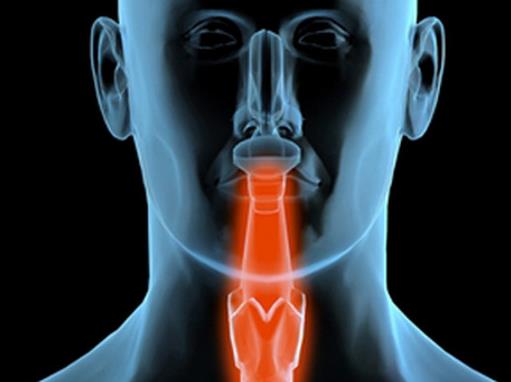

8Īóč¬░®

░ūč¬▓Ī╩Ūę╗ŅÉįņč¬Ė╔╝Ü░¹É║ąį┐╦┬Īąį╝▓▓ĪĪŻ┐╦┬Īąį░ūč¬▓Ī╝Ü░¹ę“×ķį÷ų│╩¦┐žĪóĘų╗»šŽĄKĪóĄ“═÷╩▄ūĶĄ╚ÖCųŲį┌╣Ū╦Ķ║═Ųõ╦¹įņč¬ĮM┐Śųą┤¾┴┐į÷ų│└█ĘeŻ¼▓óĮ■ØÖŲõ╦¹ĘŪįņč¬ĮM┐Ś║═Ų„╣┘Ż¼═¼ĢręųųŲš²│Żįņč¬╣”─▄ĪŻ┼R┤▓┐╔ęŖ▓╗═¼│╠Č╚Ą─žÜč¬Īó│÷č¬ĪóĖą╚Š░l¤ßęį╝░Ė╬ĪóŲóĪó┴▄░═ĮY─[┤¾║═╣Ū„└╠█═┤ĪŻ

č¬░®Š═╩Ū╚╦éā╚ń└ūž×Č·Ą─░ūč¬▓ĪŻ¼č¬░®╗╝š▀Ģ■│÷¼F▓╗═¼│╠Č╚Ą─žÜč¬Īó│÷č¬ĪóĖą╚Š░l¤ßĄ╚░YĀŅŻ¼ų╬»¤ŲüĒę▓▒╚▌^Å═ļsĪŻļm╚╗į┌ęįŪ░Ż¼ōQ┴╦░ūč¬▓ĪŠ═Ą╚ė┌╗╝╔Ž┴╦▓╗ų╬ų«░YĪŻĄ½ī”ė┌ßtīW╚ń┤╦░l▀_Ą─¼Fį┌Ż¼ęčĮøėą┴╦ų╬»¤Ą─┐╔─▄┴╦ĪŻ